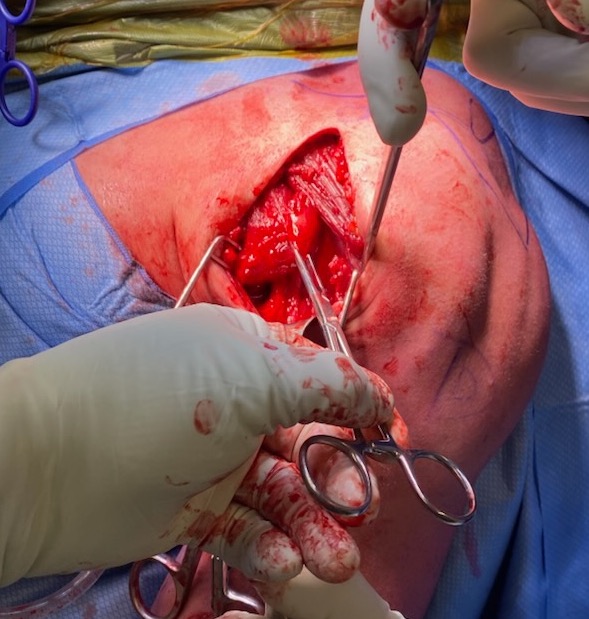

Axillary incision right shoulder

Axillary crease incision in right shoulder, with Kocher forceps on the torn pectoralis major tendon